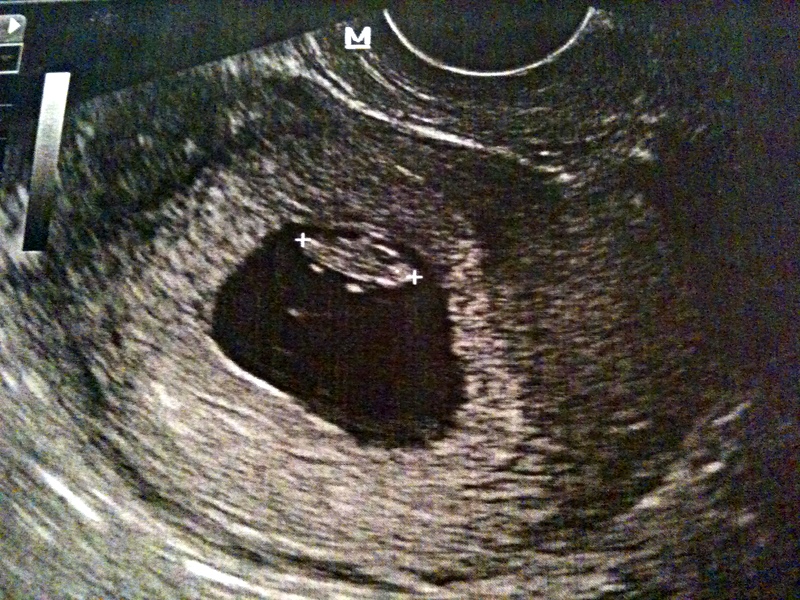

Koukli jsme se pak spolu nejdřív na obrázek a pak “živý přenos”.

“Jeden vitální plod, skoro 12 milimetrů, srdeční akce, podívejte.”

<a href=”http://vercaaivan.files.wordpress.com/2010/10/2010-09-30b.jpg”><img title=”30.9.2010 – 7 týdnů a 3 dny” src=”http://vercaaivan.files.wordpress.com/2010/10/2010-09-30b.jpg” alt=”” width=”460″ height=”345″ /></a>

Navíc, když ještě vypadá jako šiška. I když prý ta “skorohlava” je další známka, že všechno postupuje, jak má. Velice uspokojivé zprávy. Akorát ta cesta bude ještě dlouhá… a to nemyslím jen teď letadlem do Dohy.

Navíc, když ještě vypadá jako šiška! I když prý ta “skorohlava” je další známka, že všechno postupuje, jak má. Velice uspokojivé zprávy. Akorát ta cesta bude ještě dlouhá… a to nemyslím jen teď letadlem do Dohy.